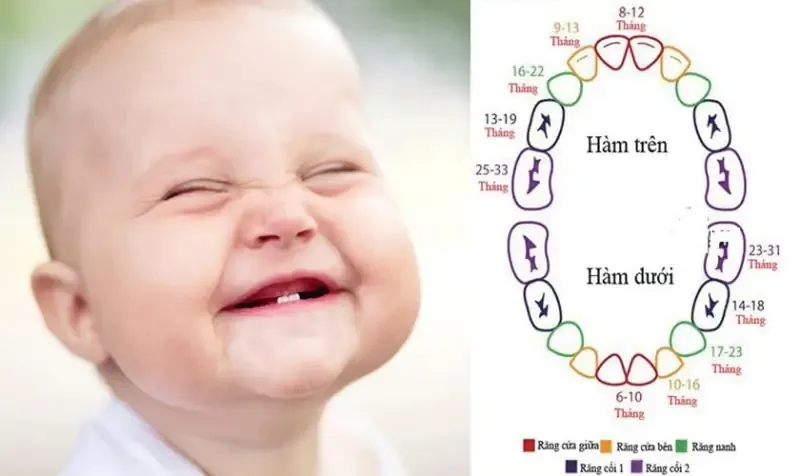

Răng ở trẻ nhỏ là một phần quan trọng trong hệ tiêu hóa và sức khỏe tổng thể của con người. Việc hiểu rõ về cấu trúc,

Câu hỏi “con nguoi co bao nhieu rang” luôn là thắc mắc phổ biến của nhiều người khi muốn hiểu rõ hơn về sức khỏe răng miệng.